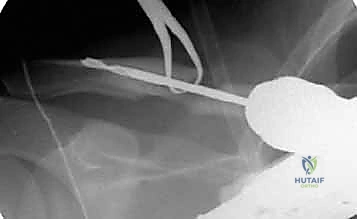

الخلاصة الطبية السريعة: تثبيت كسور الترقوة داخل النخاع (Intramedullary Fixation) هو إجراء جراحي حديث ومتطور، يستخدم مسمارًا أو قضيبًا مرنًا من التيتانيوم لتثبيت عظم الترقوة من الداخل (داخل القناة النخاعية للعظم)، مما يوفر استقرارًا ميكانيكيًا فعالًا وتعافيًا أسرع بكثير من الطرق التقليدية. يتميز هذا العلاج بكونه أقل بضعاً (Minimally Invasive)، حيث يتطلب شقوقًا جراحية صغيرة جدًا، مما يضمن نتائج تجميلية أفضل ويقلل من خطر تلف الأنسجة المحيطة. ويعد هذا الإجراء خيارًا ممتازًا ومثاليًا لحالات مختارة من كسور منتصف الترقوة المنزاحة.

في تقنية التثبيت داخل النخاع، يتم استغلال هذه القناة الطبيعية لتمرير المسمار أو القضيب المرن بداخلها، مما يجعل المسمار يعمل كدعامة داخلية (Internal Splint) تتحمل الأحمال وتشاركها مع العظم (Load-sharing)، بدلاً من تحملها بالكامل كما تفعل الشرائح المعدنية الخارجية (Load-bearing).

هذه هي التقنية المتقدمة التي يتميز بها البروفيسور محمد هطيف. بدلاً من وضع شريحة خارجية، يتم إدخال مسمار أو قضيب مرن (مثل مسمار التيتانيوم المرن TEN أو مسامير مصممة خصيصًا للترقوة) داخل تجويف العظم (القناة النخاعية).